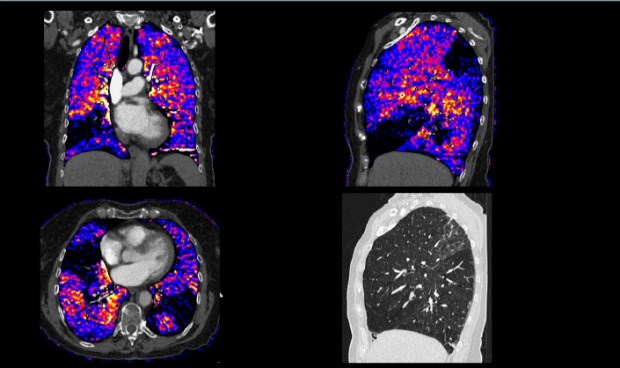

La energía dual es, para la marca, otra de sus grandes bazas, básicamente porque en ello son únicos. “Con una sola adquisición, el profesional obtiene cuatro tipos de imagen diferente: una con contraste, otra de realce de contraste, una solo del mapa de yodo y una cuarta sin contraste”. Lo que permite conocer, por ejemplo, “los tipos de cálculos renales; si son de tipo cálcico o de ácido úrico”. Una característica esencial en pacientes oncológicos, entre otros, porque permite saber la composición de las lesiones o qué tipo de tejido es. “Distingue entre necrosis y tejido tumoral, lo que reduce las cirugías y ayuda a precisar los tratamientos”, añade la compañía. Todo ello en un dispositivo de 128 cortes que logra sin problemas los estudios de percusión de órgano completo.